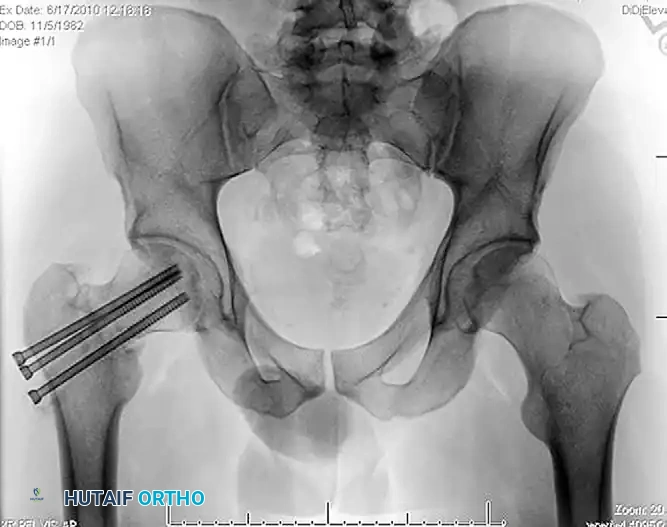

Figure: Anteroposterior radiograph demonstrating a severe varus malreduction of a femoral neck fracture following initial cannulated screw fixation.

Figure: Anteroposterior radiograph revealing an established nonunion of the femoral neck with hardware failure and backing out of the cannulated screws.